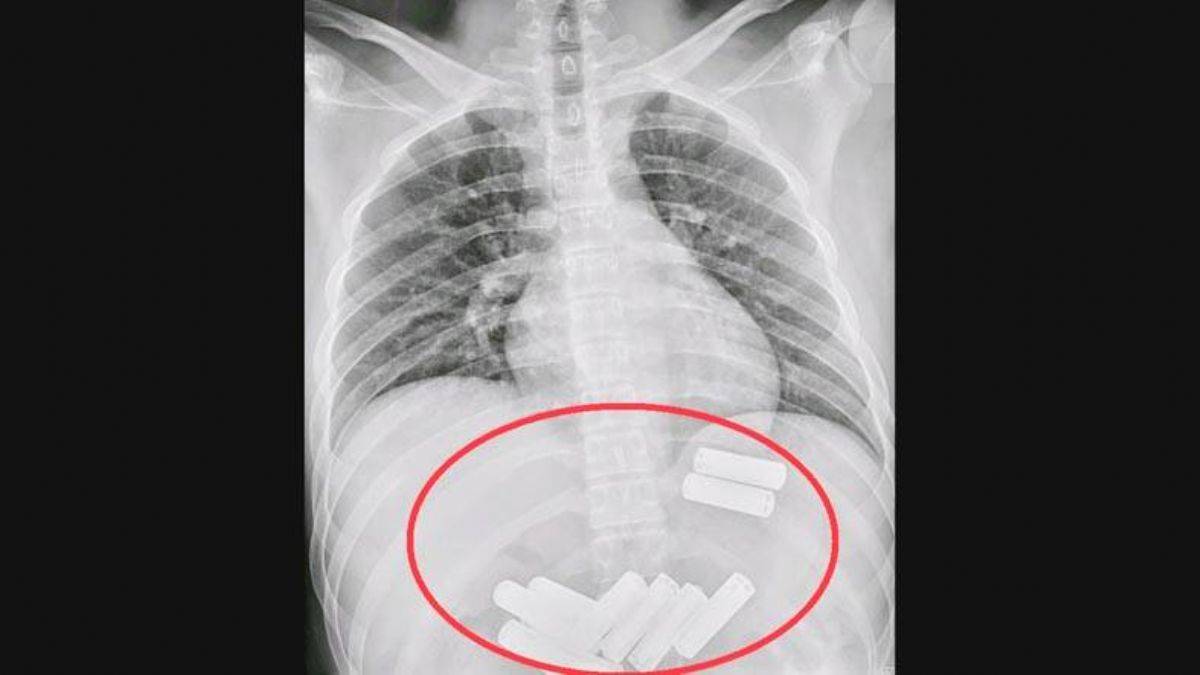

11 pil yutan Çinli: Canım çok yandı

Çin medyasında bir kişinin 11 kalem pil yutması gündem oldu.

Çin'in Miaoli bölgesinde doktorlar, bir kişinin yuttuğu 11 kalem pili endoskopi yöntemiyle midesinden çıkardı.

Çin'de 23 yaşındaki Lee, 11 pil yutması üzerine arkadaşı tarafından Mialoi bölgesindeki "Da Chien" hastanesine götürüldü.

Doktorlar, röntgen çekerek Lee'nin midesinde saptadıkları pilleri, endoskopi yöntemiyle yaklaşık bir saatte çıkardı.

Lee, endoskopi sırasında canının çok yandığını belirterek bir daha pil yutmaya cesaret edemeyeceğini söyledi. AA